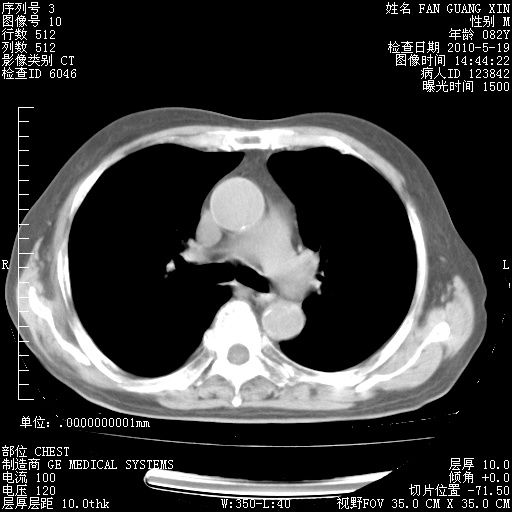

可改为口服强的松40-50mg/d治疗,若病情仍稳定,胸部阴影不再吸收可逐渐减量